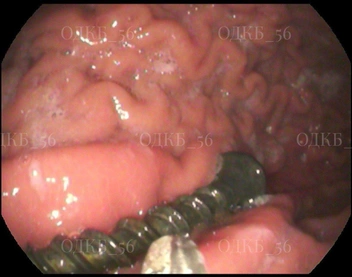

Мальчика доставили в приемное отделение ОДКБ по направлению из ЦРБ уже с результатами рентгенографии брюшной полости. Команда медиков экстренно провела ему общее обезболивание и сделала эндоскопию верхнего отдела ЖКТ. Саморез находился в двенадцатиперстной кишке, и представлял неиллюзорную угрозу развития кишечной непроходимости и пробивания кишки.

Врачи сработали филигранно: осложнений удалось избежать, инородное тело удалено, а школьник выписан домой в удовлетворительном состоянии.